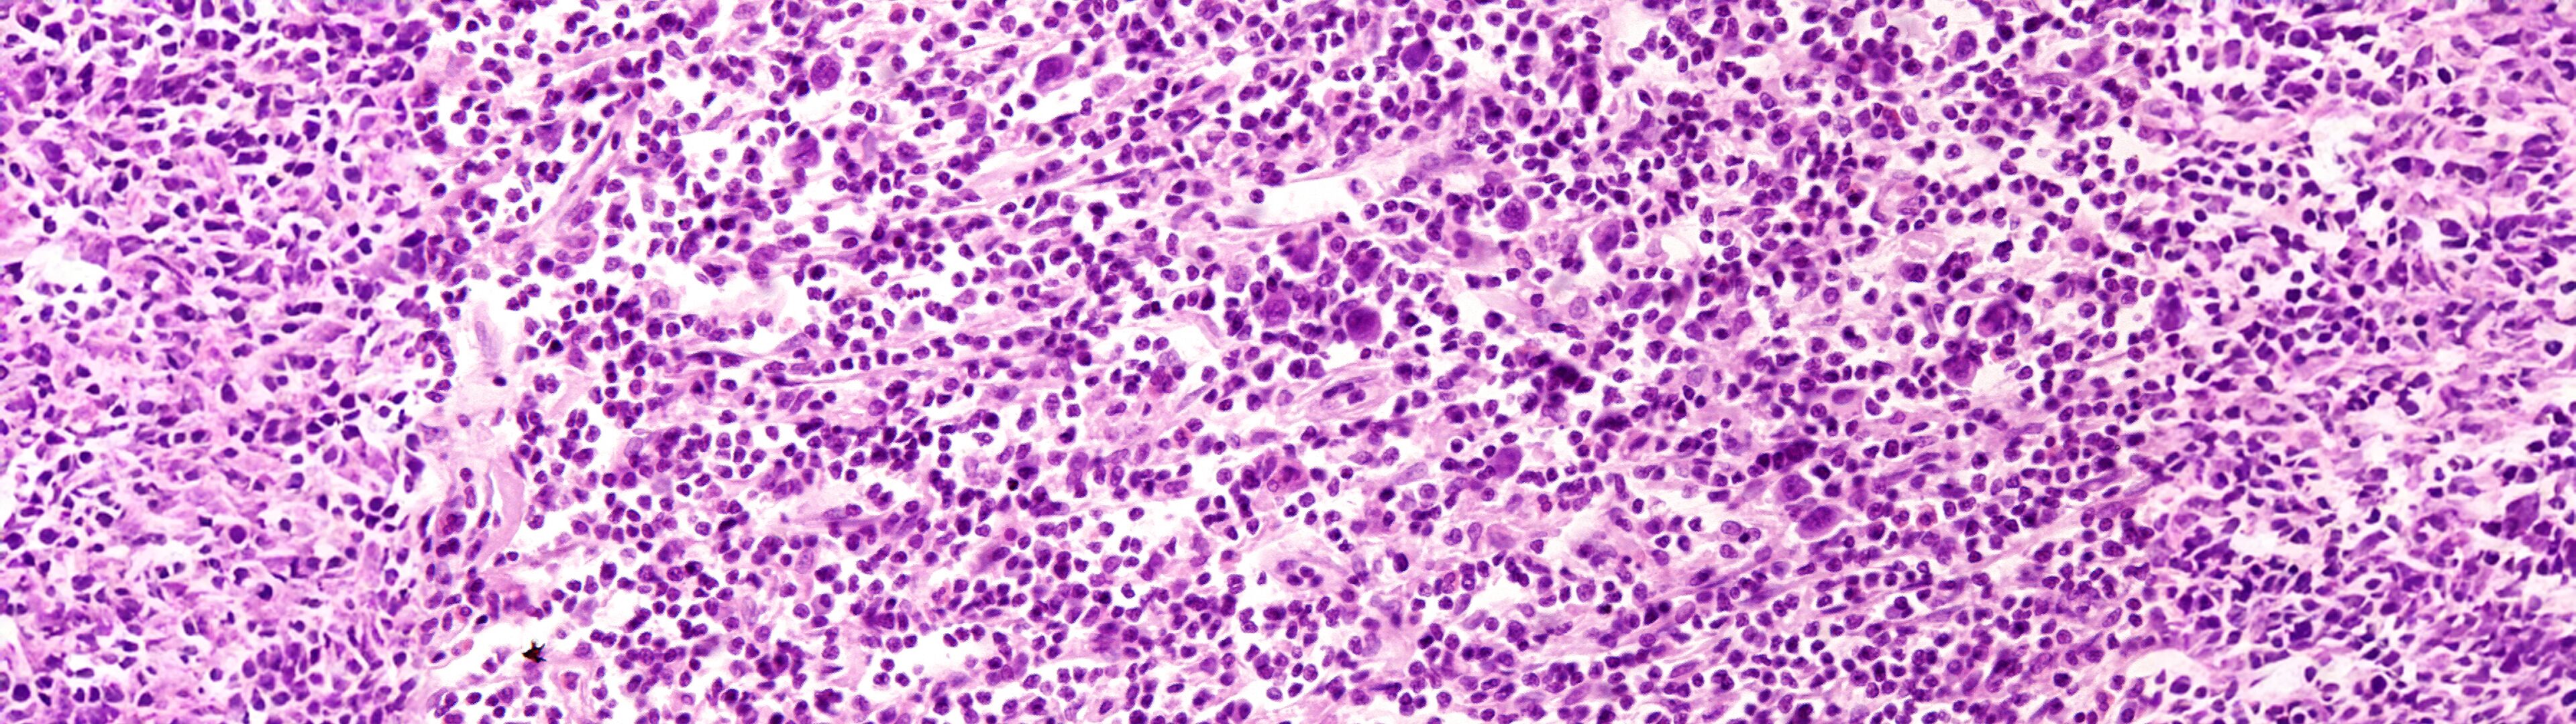

Historisch gesehen, wurden Lymphome meist mit einer alleinigen Strahlen­therapie therapiert. Durch immer bessere Chemo­therapien wird die Strahlen­therapie heut­zutage meist nur noch für residuelle also für zurück­bleibende Tumor­reste nach der Chemo­therapie angewandt. Diese Kombination führt zu optimalen Ergebnissen durch intensivere, aber gleich­zeitig schonendere Konzepte.